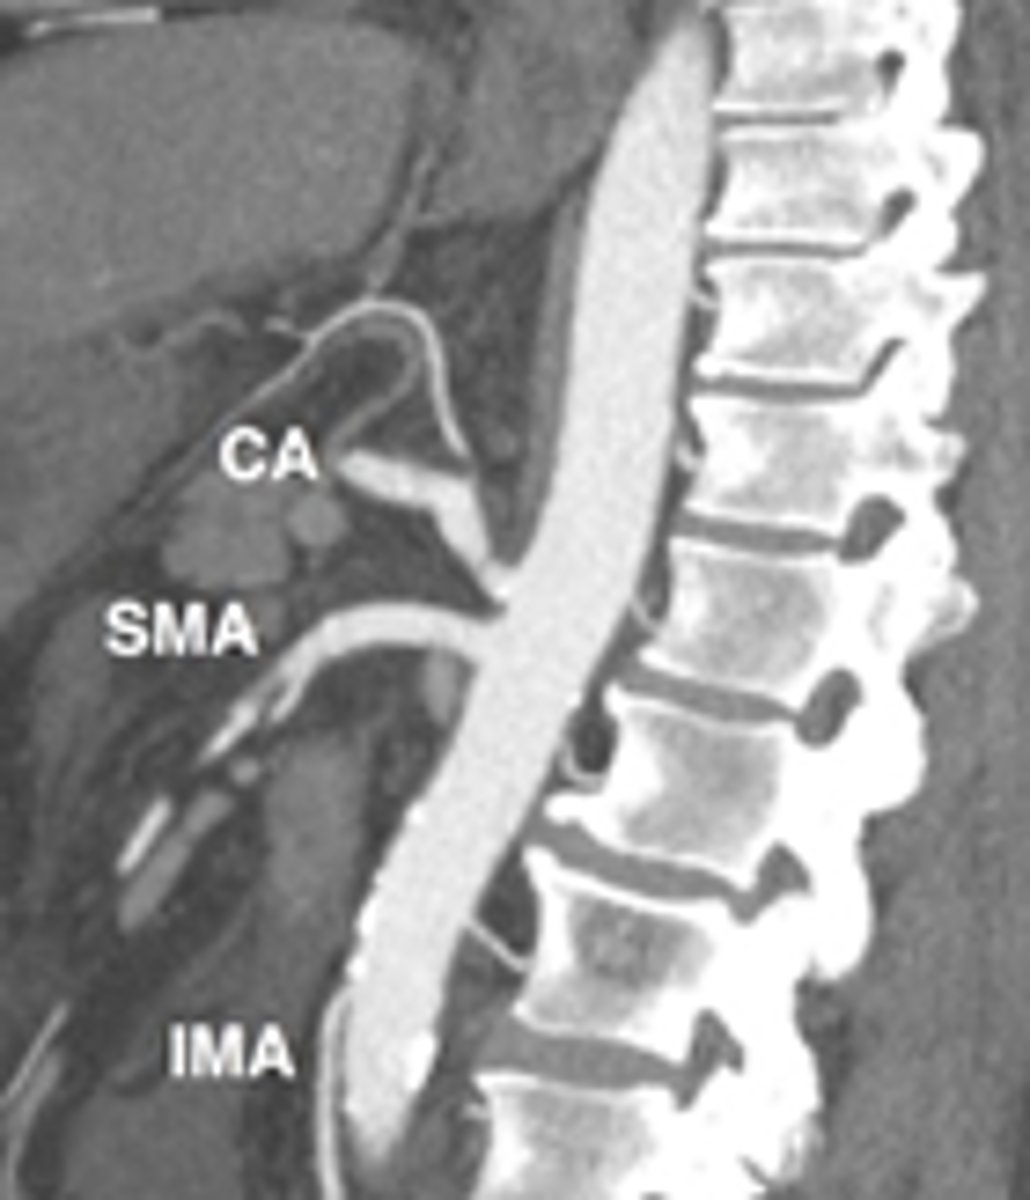

When a thrombus causes acute mesenteric arterial occlusions, which arteries are typically involved?

Both SMA & Celiac (dt collateral formation; thrombus typically forms at the take off of celiac axis or SMA)

What is the most likely etiology of Chronic Mesenteric Ischemia?

Atherosclerotic narrowing of celiac and/or SMA